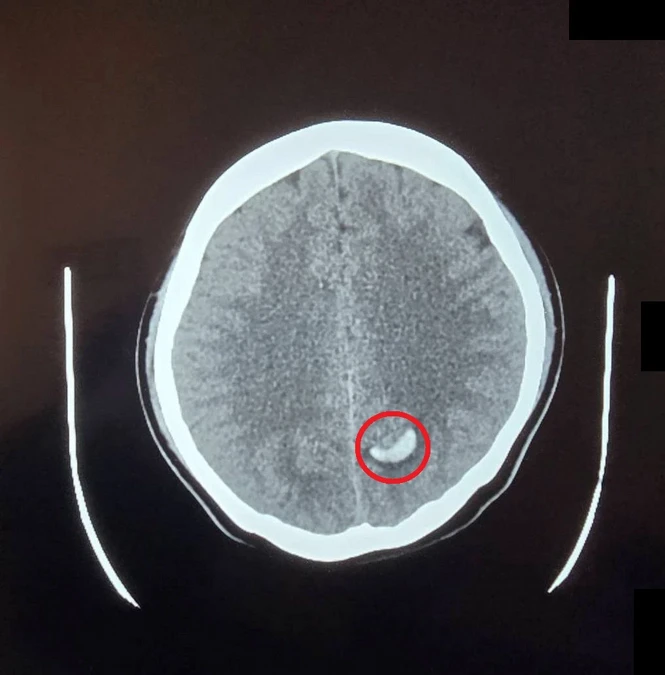

23歲的周小姐正值青春年華,卻在毫無預兆下感到一陣劇烈頭痛,隨即伴隨嚴重的頭暈與嘔吐感,家屬見狀趕緊將她送往大千綜合醫院急診。經腦部電腦斷層掃描,醫師赫然發現其左側腦部有出血跡象,且出血位置極其不尋常⋯⋯

後續,醫療團隊隨即展開精密檢查,證實為罕見的「顱內動靜脈畸形」引發出血,所幸在醫師及時進行微創血管內栓塞治療後,順利止住出血,病人症狀明顯改善,成功化解一場腦內危機。

大千綜合醫院神經放射科醫師康靜維指出,「顱內動靜脈畸形」是一種先天性的腦血管病變,在胚胎發育過程中,若動脈與靜脈之間缺乏微血管緩衝,導致高壓的動脈血流直接衝入脆弱的靜脈,管壁便會因長期無法負荷壓力而逐漸薄弱,最終像吹太大的氣球一樣破裂,引發腦出血。